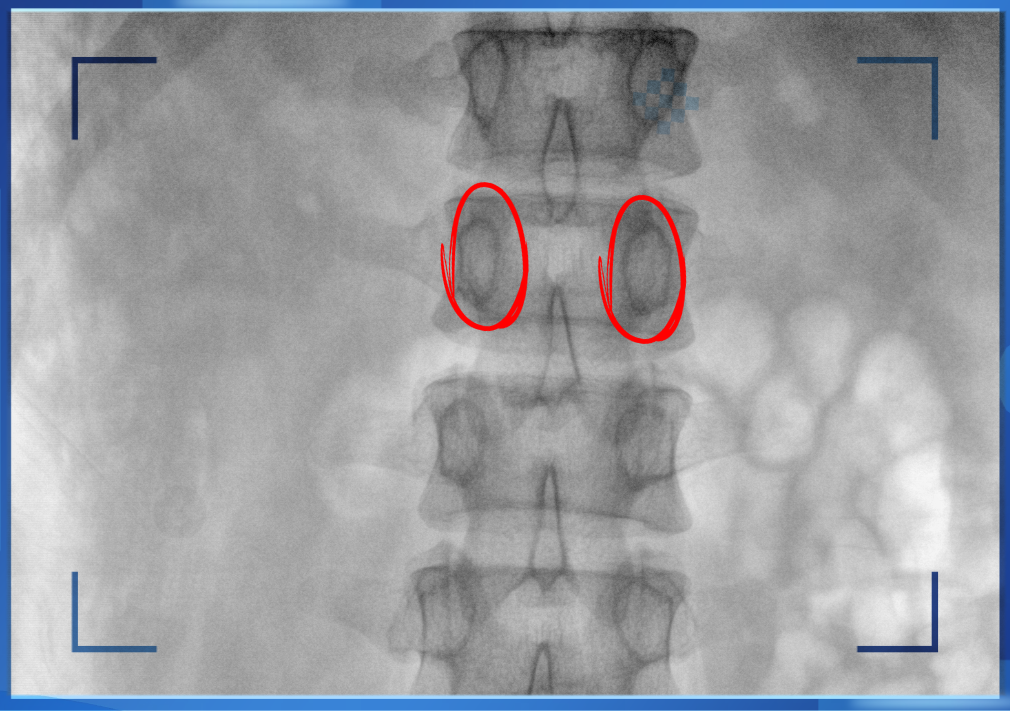

醫(yī)生通常會在“貓眼”里尋找進(jìn)針點和出針點,憑醫(yī)生的經(jīng)驗把釘子打在椎弓根里。手術(shù)比較依賴醫(yī)生的經(jīng)驗,萬一出現(xiàn)偏差對病人來講就是毀滅性的打擊。如果在復(fù)雜的手術(shù)中有三維影像的支持,確保釘子精準(zhǔn)的打在椎弓根里,可大大的提高手術(shù)操作的精度。

“貓眼”指的是椎弓根在正位的投影。